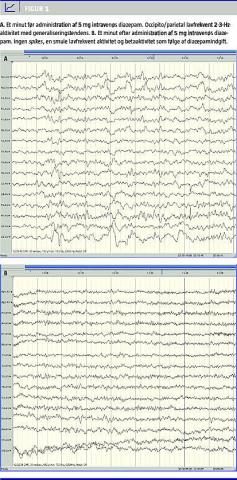

EEG-undersøgelsen var svært abnorm og forenlig med SE. Baggrundsaktiviteten var sparsom, dominant frekvens på 8 Hz og amplitude 50 mikrovolt. Occipitalt/parietalt fandtes 2-3-Hz-aktivitet, amplitude op til 300 mikrovolt, størst på højre side iblandet små spikes/sharp-waves , samt generalisering (Figur 1 A). Efter fem miligram intravenøs diazepam aftog EEG-forandringerne betydeligt, og patienten blev næsten som habituelt (Figur 1B).

De nævnte EEG-forandringer og den kognitive påvirkning, der aftager betydeligt ved diazepamadministration, er karakteristiske ved NKSE af kompleks partiel type (DG412 ) [2, 3].